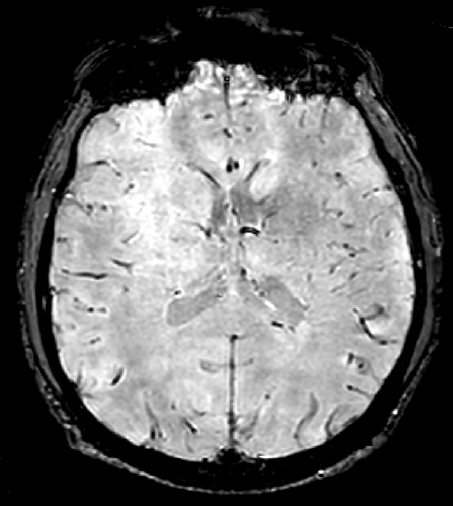

МРТ головного мозга была выполнена 19 пациентам исследуемых групп (8 пациентам группы 1, 2 — группы 2, 9 — группы 3), в том числе с использованием последовательностей SWI/SWAN. Диффузных микрокровоизлияний в веществе головного мозга обнаружено не было, что подтвердило наличие у всех пациентов легкой ЧМТ (рис. 4, 5).

Рис. 4. МРТ головного мозга в режиме SWI/SWAN пациента с ушибом головного мозга легкой степени. Кругом отмечен контузионный очаг 2-го типа в теменной доле справа. Диффузных микрокровоизлияний не обнаружено

Fig. 4. MRI of the brain in SWI/SWAN mode of a patient with mild brain injury. A type 2 contusion lesion in the parietal lobe on the right is marked in red. No diffuse microbleeds were detected

Выполнение МРТ головного мозга пациентам, подвергшимся воздействию взрыва, часто невозможно из-за наличия у них металлических осколков в теле. МРТ выполнялась на томографе с напряженностью магнитного поля 1,5Т. Возможно, относительно низкая разрешающая способность по сравнению с томографом 3Т послужила причиной недиагностированных диффузных микрокровоизлияний в веществе головного мозга у пациентов с легкой ЧМТ вследствие воздействия взрыва. Однако отсутствие изменений по данным МРТ, в том числе с использованием импульсной последовательности SWI/SWAN (взвешенной по магнитной восприимчивости), может свидетельствовать и о наличии протекторных свойств средств индивидуальной бронезащиты (шлема) при воздействии на организм факторов взрыва.